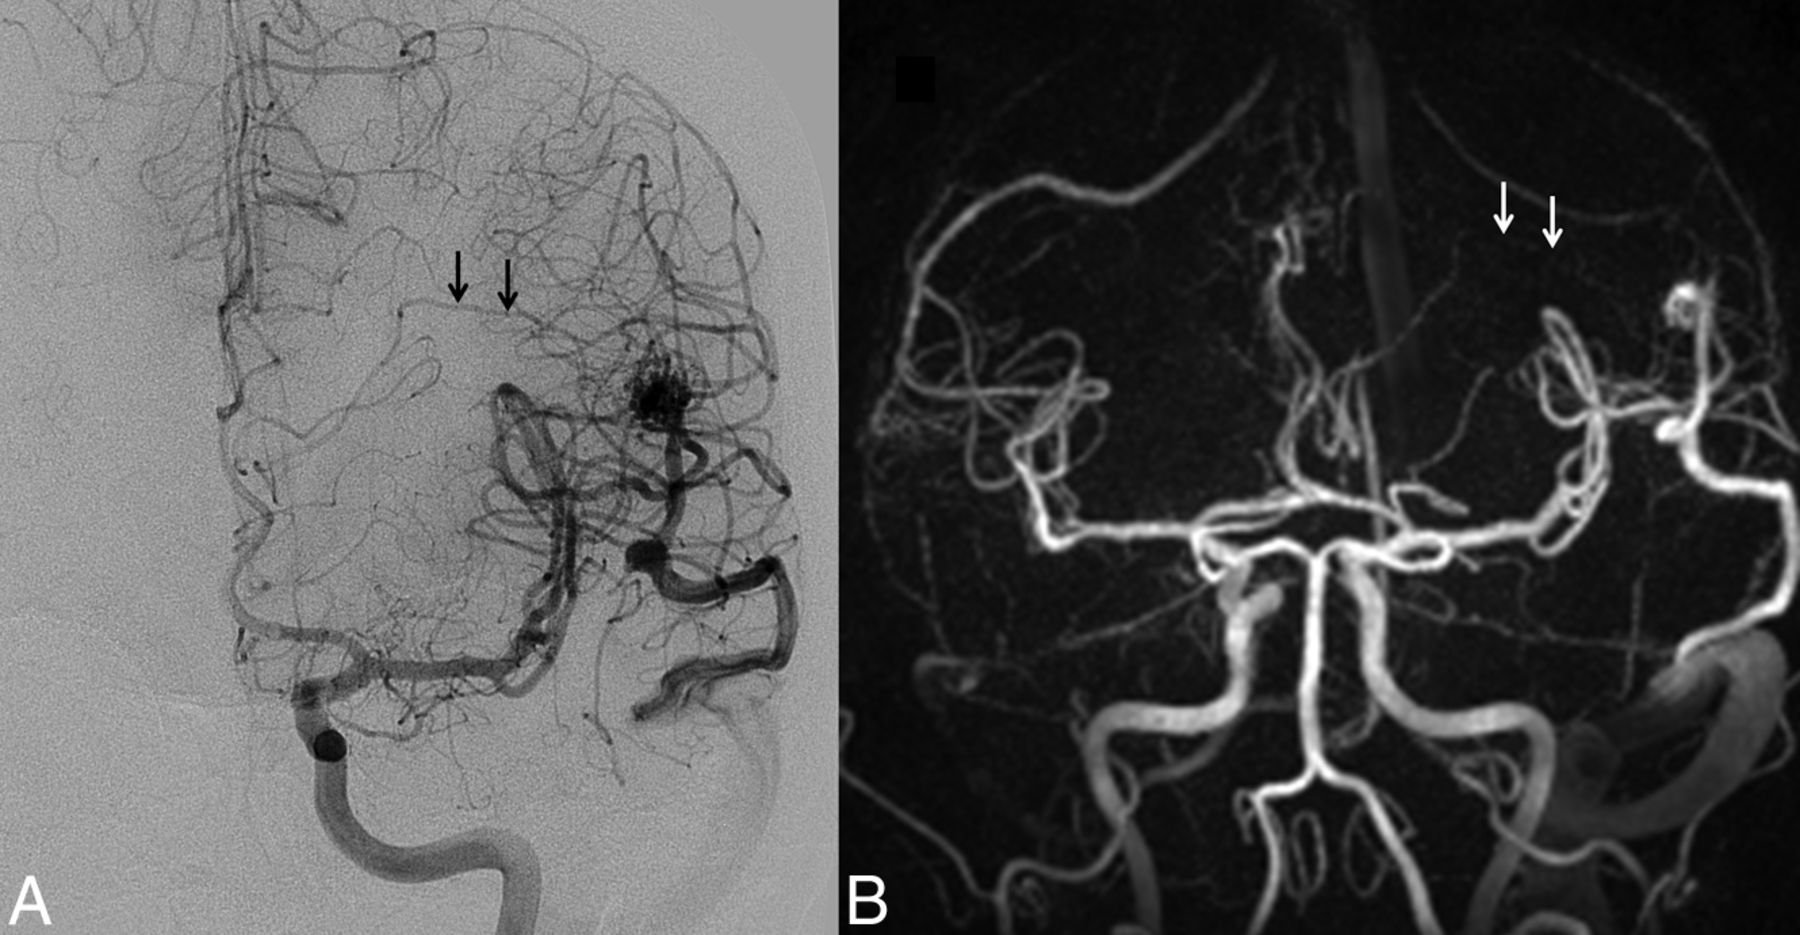

The same patient as shown in Fig 3. Top row: HYPRFlow images in the sagittal plane: arterial (A), mixed (B), and venous phase (C). Bottom row: corresponding DSA images: arterial (D), mixed (E), and venous phase (F). Note the excellent correlation of the arterial supply and venous drainage pattern.

When we compared M2/M3 arterial branches, there was no significant difference between the mean image quality scores of HYPRFlow (3.18) and TOF (3.26) (P > .05), but there were very significant differences between the image quality of both HYPRFlow and TOF compared with DSA (3.94) with P < .002 and .004, respectively. DSA deep and superficial venous image quality (3.82) was significantly better than HYPRFlow (3.08) (P < .005) (Figs 2⇓–4).